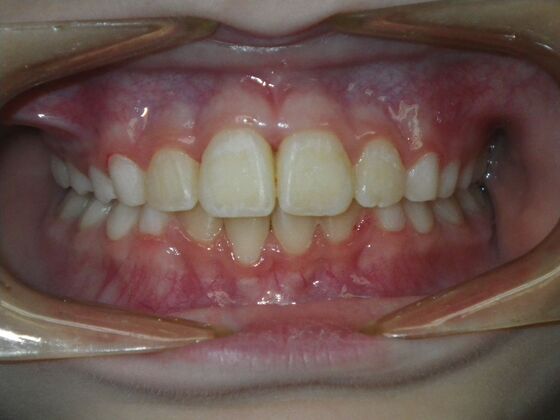

This sweet patient presented with constricted upper and lower arches and blocked out, rotated upper and lower anterior teeth. The upper centrals were leaning backward and had the lower arch captured preventing anterior advancement. Treatment was begun on the upper arch first, followed with placement of lower lip bumper to allow for lateral and anterior development of lower arch. Eventually placed lower brackets with strategic slenderizing of primary teeth to allow permanent incisor to assume their proper placement. All accomplished within 12 months and straight-wire appliances.